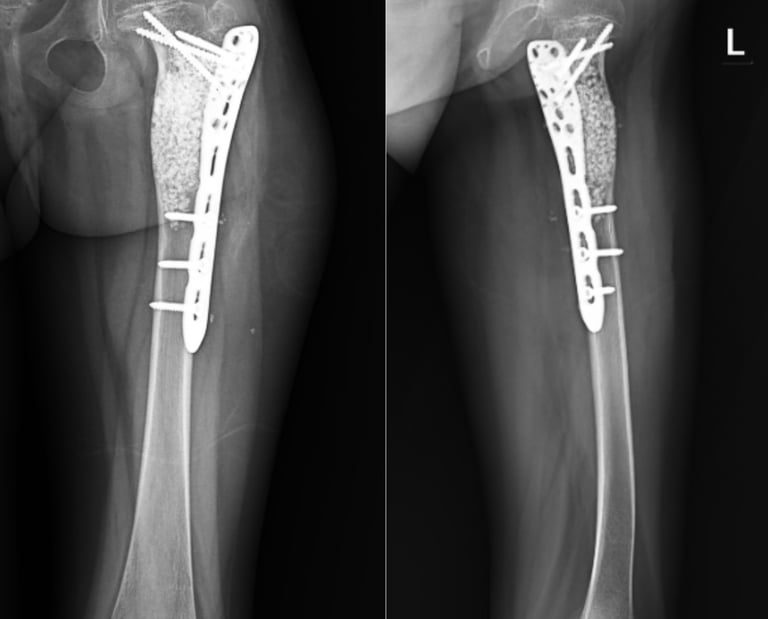

Combination-type periprosthetic tibial fracture: Felix type (II+IV)A

Tibial periprosthetic fractures are rare but present a complicated problem for orthopaedic surgeons. Literature in relation to combination-type periprosthetic fractures is extremely scarce, and there is limited guidance available on its treatment. We report the case of a woman in her 60s, whose radiographs revealed a periprosthetic fracture of the tibia, which was a Felix type (II+IV)A fracture. Our demonstrated treatment of a Felix type II+IV periprosthetic fracture could be a viable treatment option for such fractures.